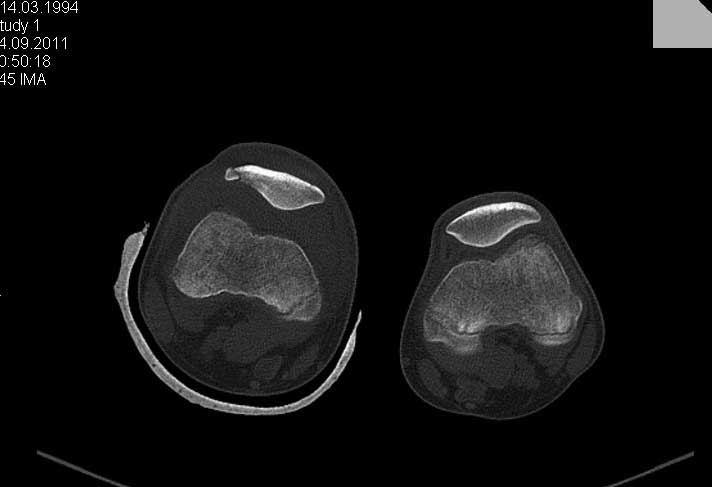

Перелом надколенника.

Обратился ребёнок 15 лет с оскольчатым переломом надколенника. Давность травмы 1 неделя.Поделитеся пожалуйста опытом.

1. Надо ли оперировать?

2. Не ухудшит ли спице-проволочный шов стояние отломков.

3. Может не оставить так и лечить консервативно?